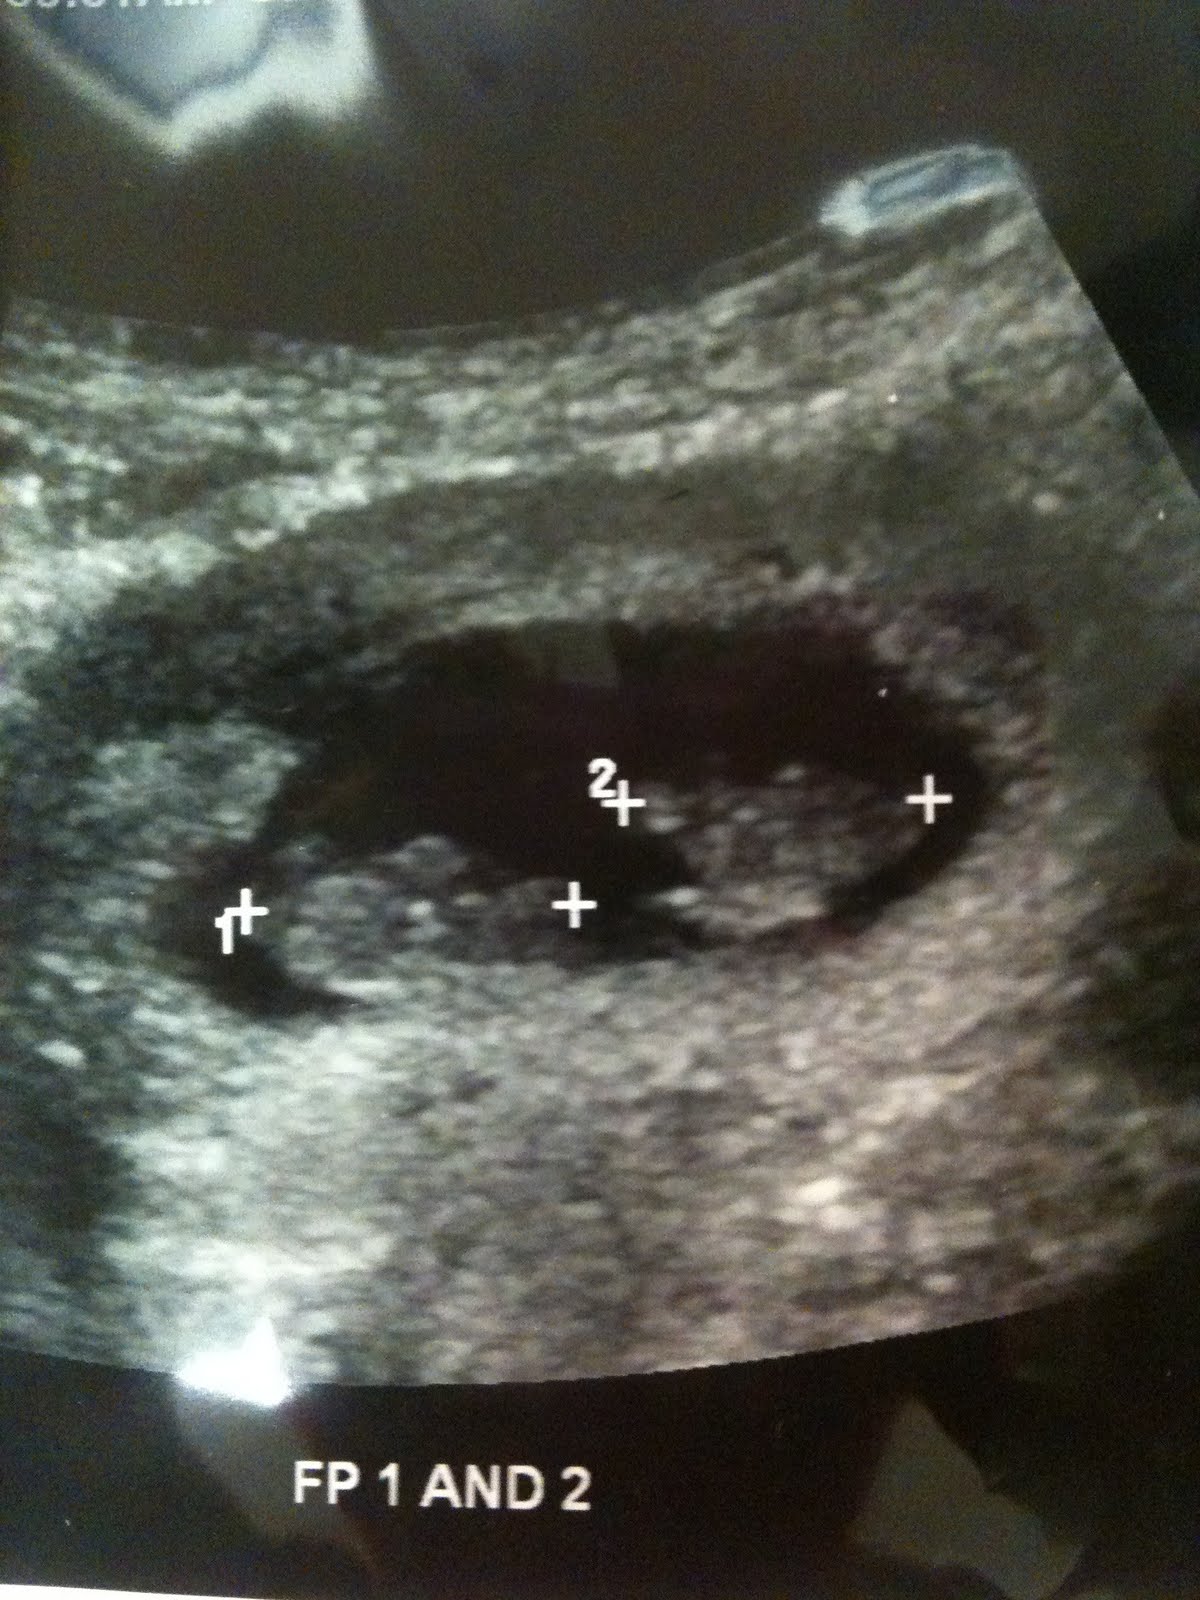

7 Week Ultrasound Fraternal Twins

7 Week Ultrasound Fraternal Twins What Do Twins Look Like On Ultrasound At 7 Weeks Medically reviewed by valinda riggins nwadike, md, mph, ob/gyn, — written by sarah bradley on october 30, 2020. So if you’re having an ultrasound at seven weeks, keep an eye out for the second baby! What do twins look like on ultrasound at 7 weeks? Read on to learn about twin fetal development and see some incredible twin. 7 weeks. What Do Twins Look Like On Ultrasound At 7 Weeks.

7 Week Ultrasound Fraternal Twins What Do Twins Look Like On Ultrasound At 7 Weeks Yes, we can see twins at 7 weeks, and we should be able to tell you the type of twins they are. Read on to learn about twin fetal development and see some incredible twin. Your twins hearts should be beating at. 7 weeks ultrasound twins at seven weeks, it’s usually relatively easy to see if you’re having twins. 7. What Do Twins Look Like On Ultrasound At 7 Weeks.

7 Week Ultrasound Fraternal Twins What Do Twins Look Like On Ultrasound At 7 Weeks Read on to learn about twin fetal development and see some incredible twin. 7 weeks ultrasound twins at seven weeks, it’s usually relatively easy to see if you’re having twins. Medically reviewed by valinda riggins nwadike, md, mph, ob/gyn, — written by sarah bradley on october 30, 2020. 7 weeks pregnant with twins ultrasound pictures. So if you’re having an. What Do Twins Look Like On Ultrasound At 7 Weeks.